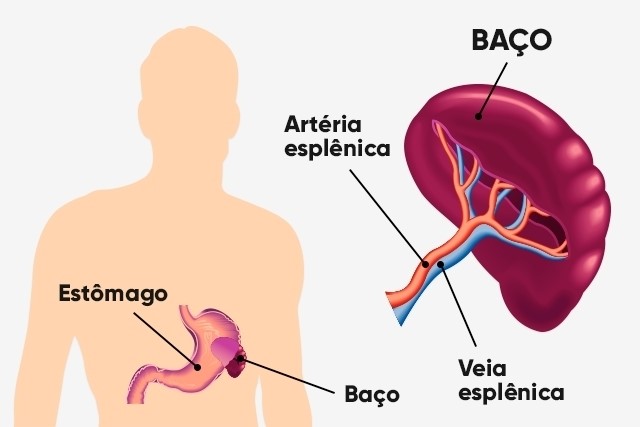

BAÇO

Quando se pensa em baço e sistema imunológico, percebemos que a participação do mesmo nesse sistema é bem conhecida. O baço é o principal responsável pela fagocitose e pela depuração de partículas, bactérias, vírus, fungos e parasitas da corrente sanguínea (8).

O baço encontra-se situado atrás do estômago e filtra o sangue da mesma forma como os nódulos linfáticos filtram a linfa e coletam antígenos, assim como também captura e se desfaz de células vermelhas senescentes.

A massa principal deste órgão é composta pela polpa vermelha e os linfócitos circundam as arteríolas que o penetram, formando ·áreas da polpa branca, cuja região mais interna é dividida em uma camada linfoide periarteriolar, contendo principalmente células T e revestidas por uma coroa de células B (8).

O Baço: Localização e Vascularização.